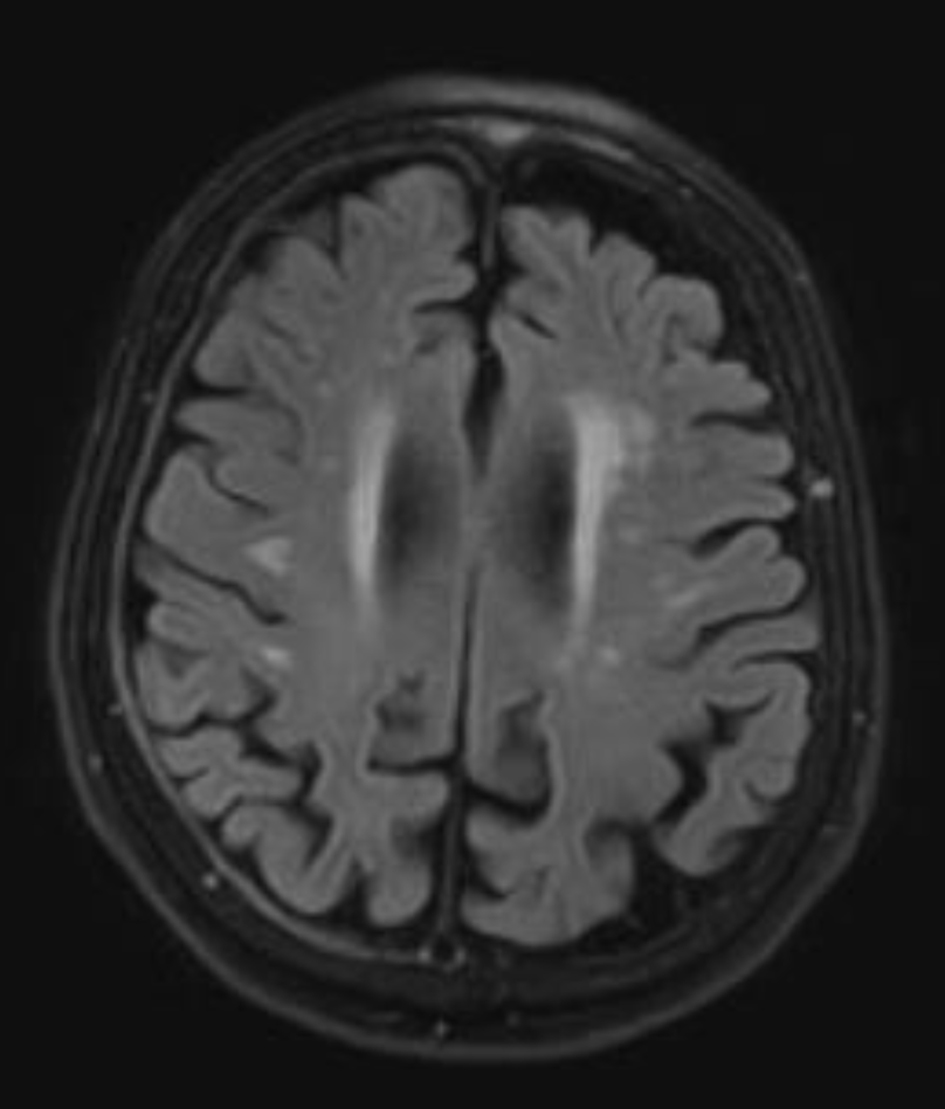

By the 4-month mark, her symptoms appeared stable to her, although her husband observed a continued mild progression. Around this time, a magnetic resonance imaging (MRI) was obtained, which revealed a small (2 mm) chronic right holohemispheric subdural collection with fluid attenuated inversion recovery (FLAIR) hyperintensity, along with mild-to-moderate cerebral atrophy and chronic microvascular ischemic changes (Fig. 2). She was started on a low dose of topiramate, 25 mg twice daily, and used the medication for approximately 3 months before it was gradually tapered and discontinued. During this period, she also participated in supportive physical therapy for functional recovery.

Figure 2. Axial T2-fluid attenuated inversion recovery magnetic resonance imaging of the brain performed on October 10, 2024, reveals a small (2 mm), chronic-appearing, mildly enhancing right holohemispheric subdural collection. In addition, mild-to-moderate cerebral atrophy and chronic microvascular ischemic changes are present.